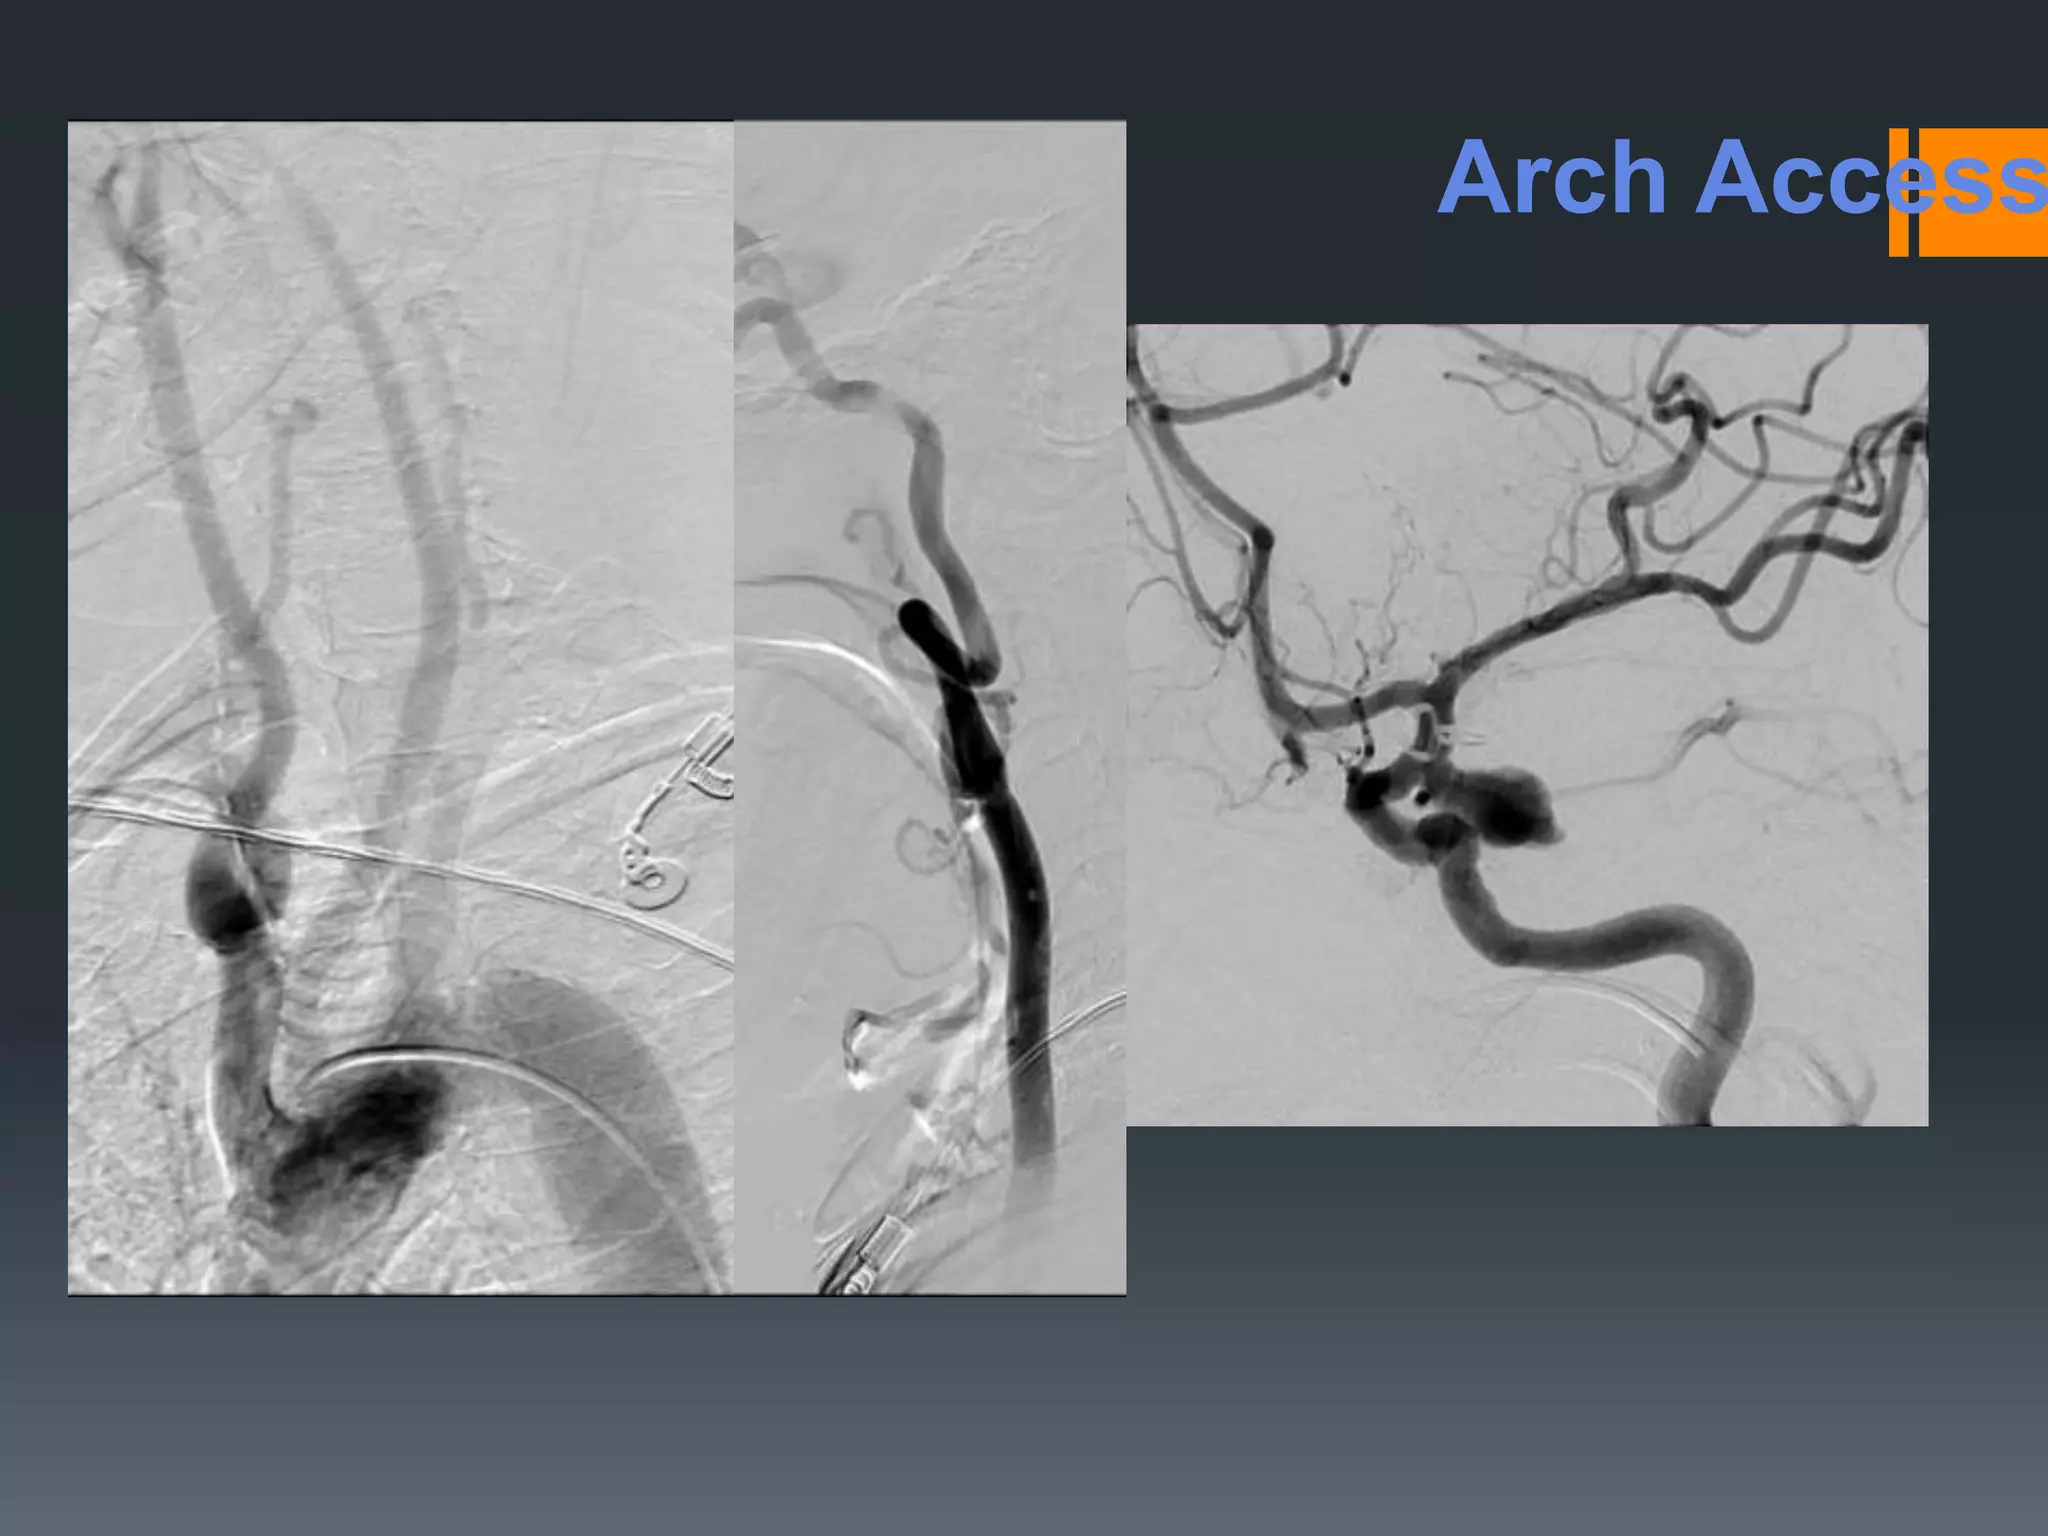

This document discusses tricks and techniques for difficult cannulations during neurointerventional procedures. It outlines strategies for accessing the aortic arch, internal carotid artery (ICA), and areas distal to aneurysms. Long sheaths, distal access catheters, and co-axial techniques are presented as options that have improved cannulation success. Guidance on sheath and catheter selection is provided for different vessel paths. The importance of catheter placement as high as possible in the ICA is emphasized. Reverse curve cannulations are also mentioned. Overall, the document stresses that careful cannulation is critical for procedural success and different strategies may be needed depending on the vessel target.